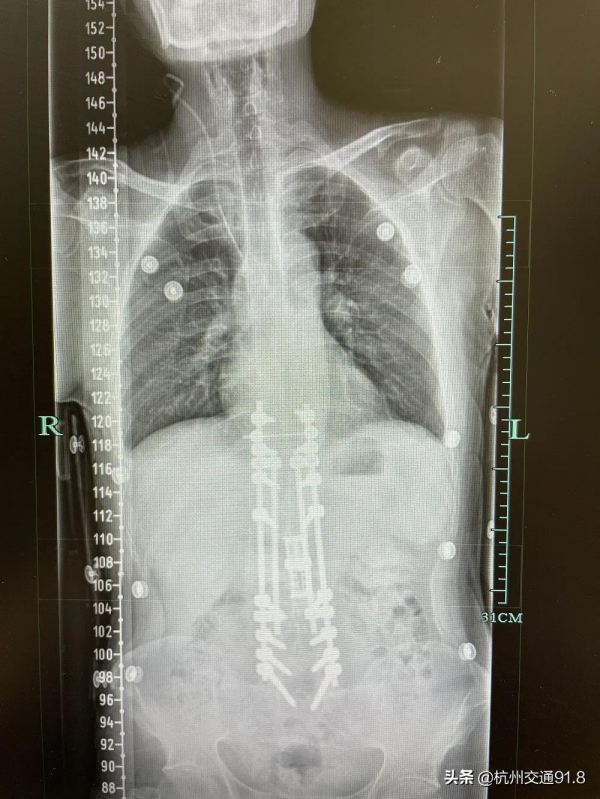

伍峻松副主任對小唐進行了仔細的查體,併為他安排了相關檢查。看到CT結果,伍峻松副主任也吃了一驚——小唐腰椎的椎體已被嚴重破壞,剩餘的骨質無法支撐,使得腰椎旁又額外長出了一塊“骨頭”(身體的一種自我保護機制),來支撐著身體,而這塊骨頭也正是小唐背上凸起的那個大包。

用人工椎體替代!伍峻松副主任精心設計了手術方案,選用合適的人工椎體。“又遇到了新問題,就像你在基座上要搭一個新柱子,結果這個基座也被破壞得歪歪斜斜,根本放不平柱子,還要想辦法造一個平穩的‘人工基座’出來。”

漫長的手術過程中,每一步都驚險萬分:清除多餘的骨骼、“打下”穩定的“基座”、精準放入人工椎體、對脊柱進行矯正復原……每個人都捏了一把汗,手術專家一步也不敢放鬆,每一次下手都是慎之又慎。最終,手術順利完成。

專家為小唐重新撐起了生命之柱